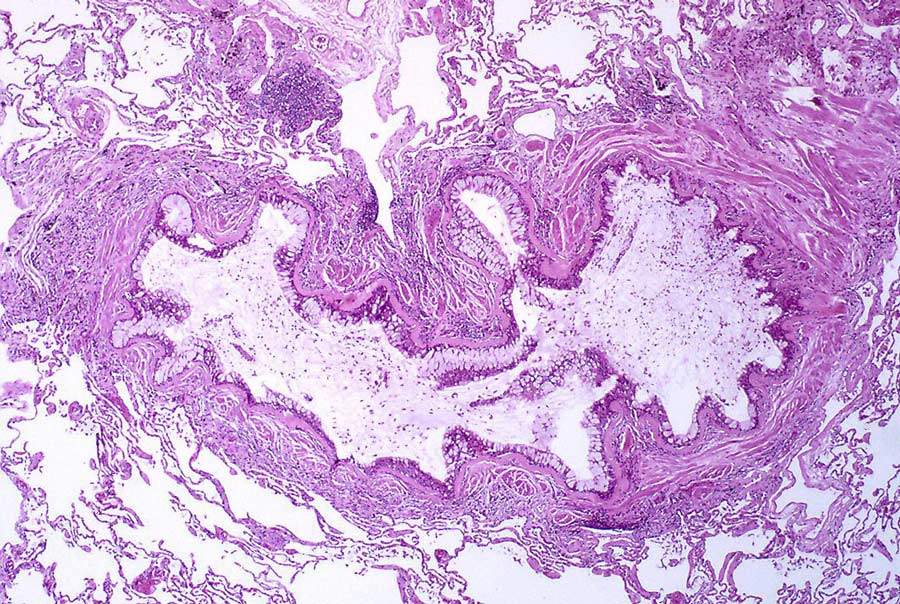

条件由肺小气道炎缩引起,导致哮喘特征症状,包括咳嗽、heezing、呼吸短促和胸部紧闭多数哮喘患者可用吸入药处理状况

研究人员解释MiRNA水平差异从有哮喘和无哮喘人的气道中检测出举例说,前几期研究将MiRNA介导基因表达式下降与哮喘病理生成相联这表明MiRNA分子在调控哮喘和哮喘症状方面可能起重要作用。